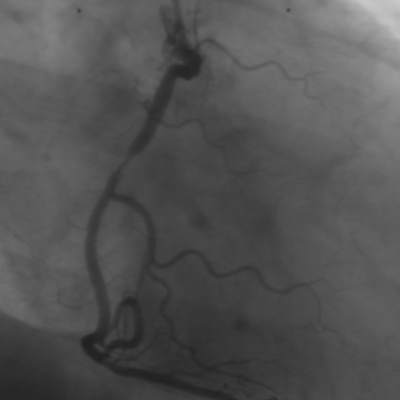

原图:血管X_光图像

检测效果